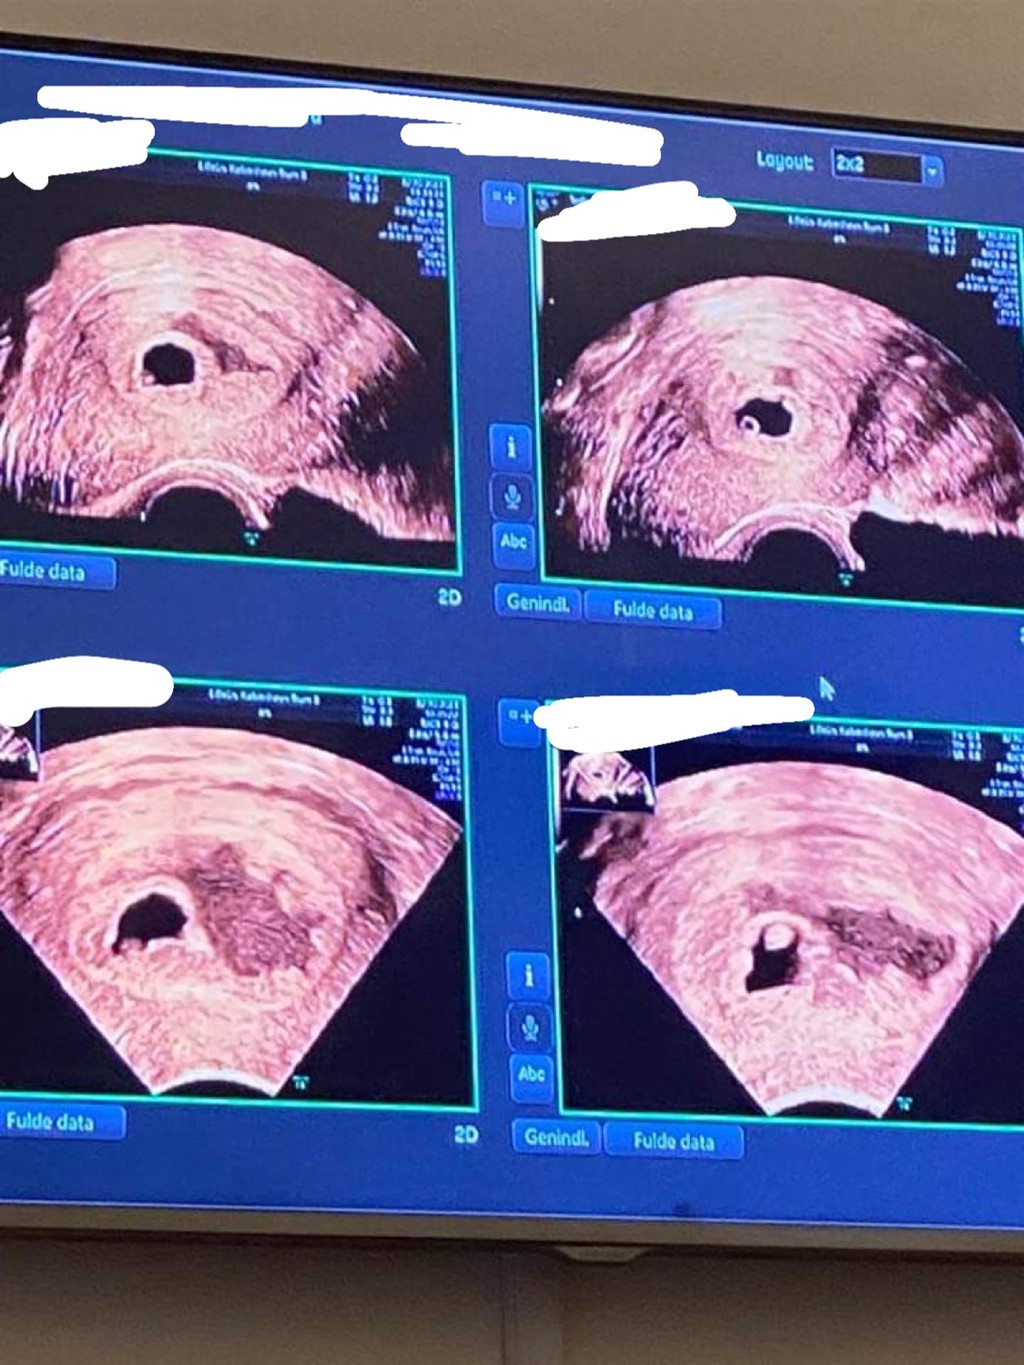

Jeg er i dag 7+1, fik min første positive test d.3.09, og har været til scanning.

Hun kunne ikke se et hjerteblink eller nærmest et foster, og hun kunne se blødning bagved.. Jeg bløder ikke endnu, men har mega mange smerter i maven, sådan murren agtig konstant.

Vedhæftede fotos (klik for at se i fuld størrelse)